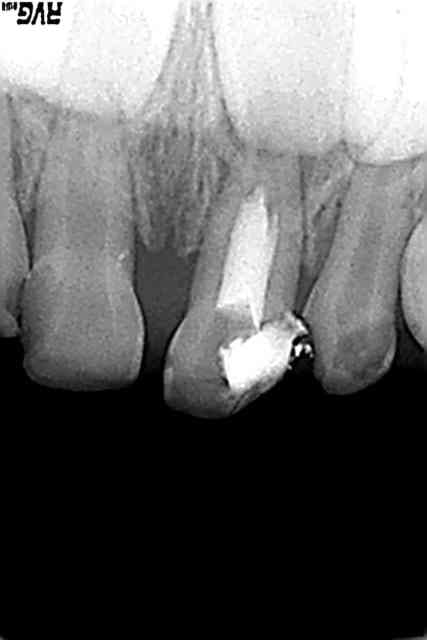

le soucis etant de decider ou non la conservation de vitalité. Dans ce cas là, l'image radio de la corne pulpaire distale n'augurait plus d'un potentiel de reparation rassurant d'autant qu'il est probable que la dent entame son processus de fonte

à priori on est en stade 2 limite début 3

pas d'atteinte de la furcation et pathologie pulpaire avec nécrose

oui, c'était bien le stade le plus delicat a determiner, encore que meme en phase terminale de stabilité, le pronostic reste le meme

atteinte pulpaire, sans necrose cependant (heu...pour l'instant...je verrai apres mon passage!)

effectivement a la radio,cas limite pulpo-pulpec

Le problème sur cette dent était si j'ai bien compris de savoir quel était le traitement approprié?

Cliniquement il n' y a pas de signes de fistules , pas de douleurs à la percussion je pense.

Radiologiquement pas de signes de foyer infectieux.

Ou bien la dent est vitale et j'opte pour la pulpotomie à l'eugénate sans fixer la pulpe , ou bien la pulpe est nécrosée et j'essaie de faire une aussi belle pulpectomie que celle réalisée par Delmo.